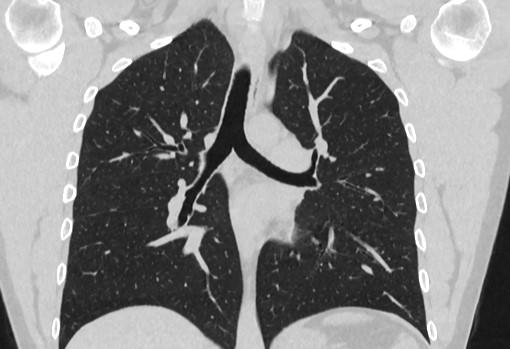

Фотографии и снимки КТ легких без контрастных веществ

Раздел: Визуальный дайджест